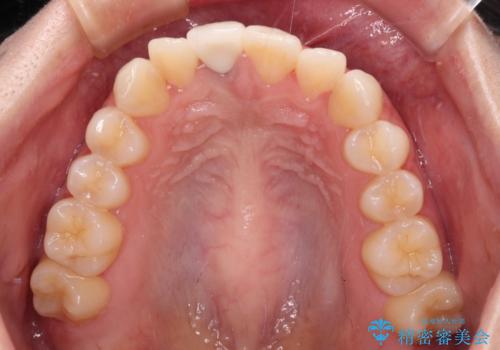

- 虫歯により神経を取り除いた前歯の変色が気になるとのことで来院された患者様です。

レントゲン写真より、歯根の炎症が認められなかったため、ファイバーコアによる土台築製後、オーダーメイドタイプのオールセラミッククラウンにて補綴することとしました。

あっという間に気になっていた変色が解決し、早く治療を始めれば良かったとおっしゃっていました。

オーダーメイドタイプのクラウンを選択いただいたので、まるで天然の歯と見間違うほど自然に仕上がり、患者様には大変満足していただきました。